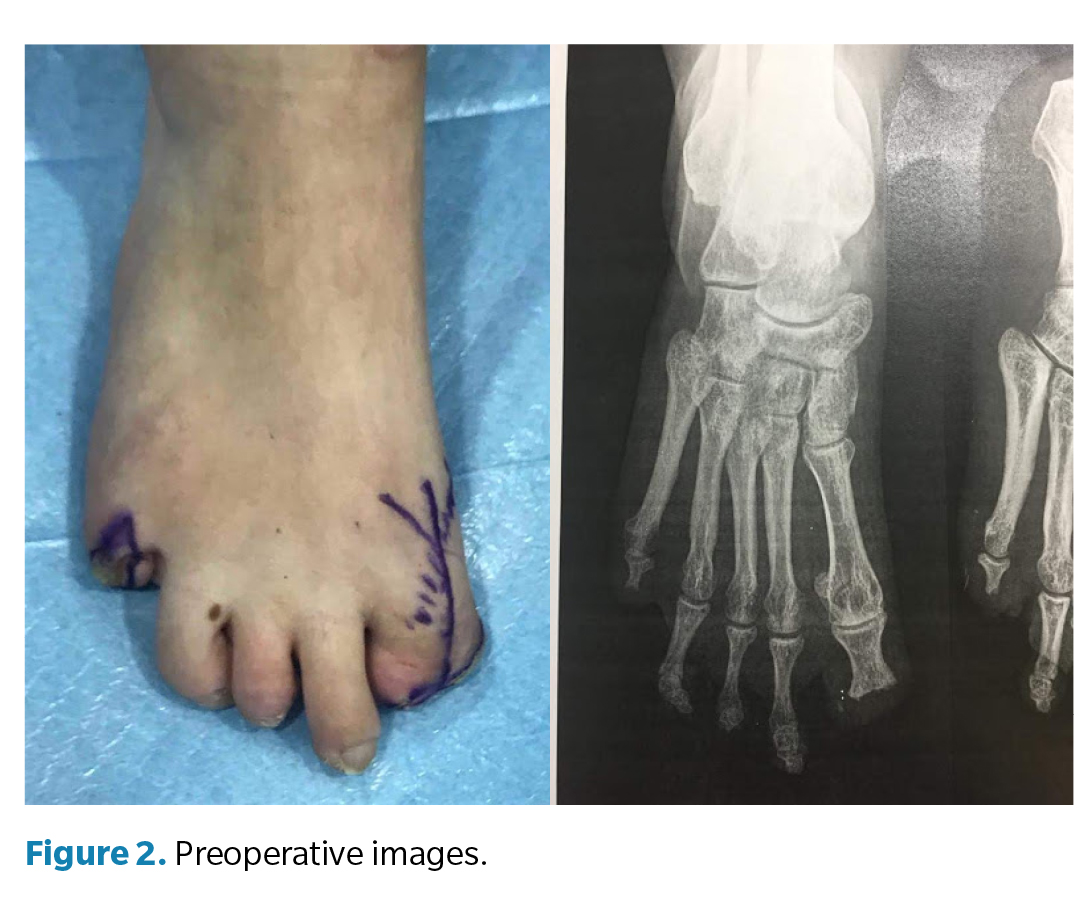

En la exploración clínica (Figura 2) del pie derecho se observó una primera articulación metatarsofalángica rígida, con el hallux en posición de flexión plantar fija y sin falange distal, lo que generaba un muñón doloroso y una alteración de la palanca propulsiva durante la marcha. La deformidad se interpretó como consecuencia de un acortamiento y fibrosis cicatricial postamputación a nivel del flexor residual, sin tracción funcional distal. Se constató dolor por apoyo directo en el pulpejo residual del primer dedo, deformado y con movilidad articular limitada pero presente. El quinto dedo derecho presentaba una cicatriz hipertrófica dolorosa con heloma residual, secundaria a la amputación completa. En el pie izquierdo, la inspección mostró cicatrices normotróficas en los sitios de amputación parcial de los dedos segundo y tercero, sin dolor ni signos de sobrecarga plantar, por lo que no se indicó tratamiento quirúrgico.